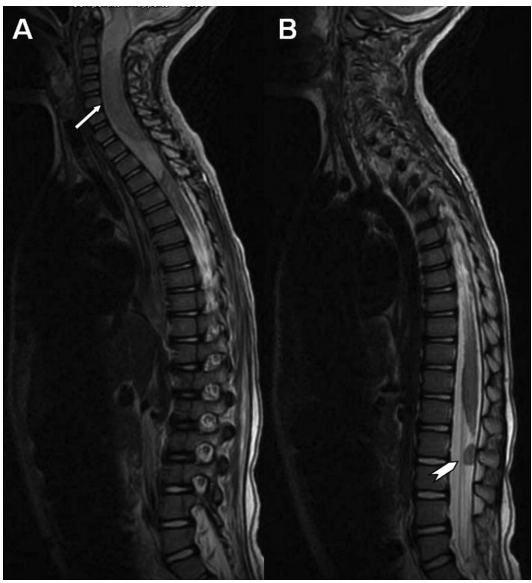

圖示:t2加權(quán)矢狀面磁共振成像(MRI)。A,腫瘤(箭頭)呈低密度,表現(xiàn)為尾部和吻側(cè)高強(qiáng)度水腫。B,注意硬膜囊(箭頭)背側(cè)表面的脊柱側(cè)凸和轉(zhuǎn)移。